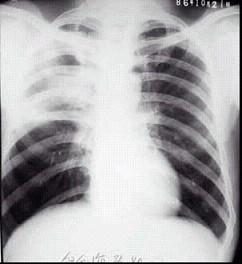

问题 皮肤疖痈患者因劳累后畏寒,高热,自服抗生素1周后无缓解,出现咳嗽、咳痰,伴发热。胸示片:右上肺可见大片状致密阴影,其间可见液平(如图)。该患者最可能的诊断是 ( )

选项 A.吸入性肺脓肿 B.细菌性肺炎 C.继发性肺脓肿 D.阿米巴肺脓肿 E.血源性肺脓肿

答案 E